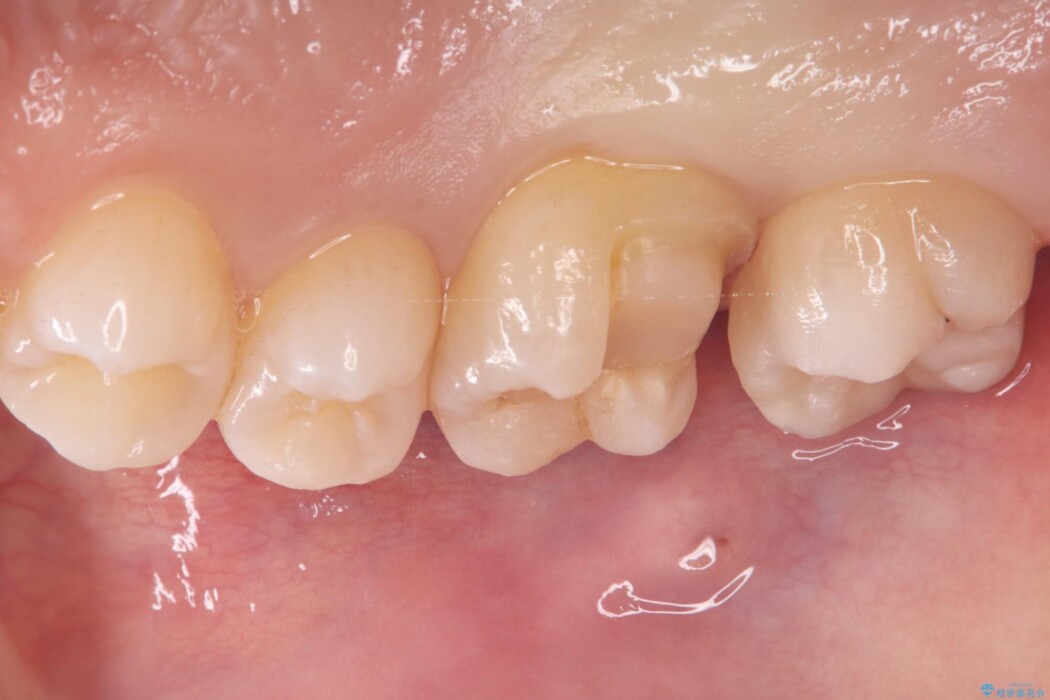

右上奥歯が欠けてしまい来院されました。

右上6番の舌側が欠けてしまっている状態でした。

破折リスクを考慮し、セラミックアンレーで治療を行うこととしました。